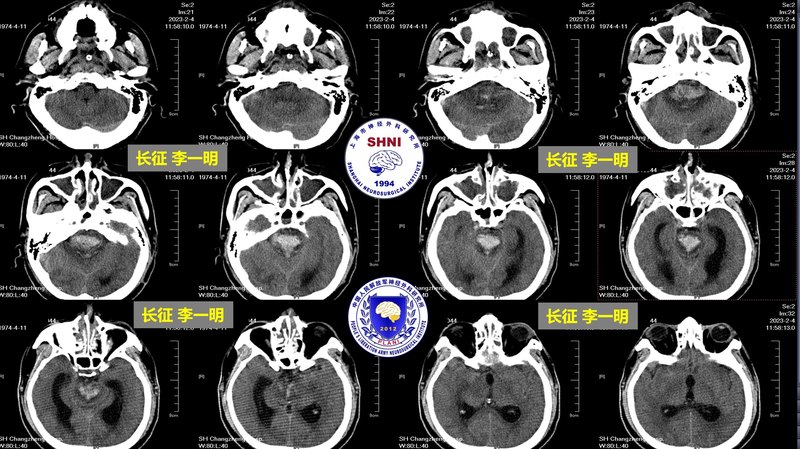

腦干出血的機(jī)器人外科手術(shù)

這是一個(gè)家庭的頂梁柱,男性,45歲,江西彭浙縣人,2月2日夜間飲酒后突發(fā)昏迷,在當(dāng)?shù)蒯t(yī)院就診,發(fā)現(xiàn)是腦干大量出血,當(dāng)?shù)蒯t(yī)院“宣判了死刑”,聯(lián)系了我們,為了“博取一線希望”,2月3日連夜從江西趕到長征來。2月4日上午救護(hù)車送到長征急診室時(shí),患者深昏迷,雙側(cè)瞳孔不等大,生命體征極度不穩(wěn)定,沒有自主呼吸,呼吸機(jī)維持呼吸,血壓260/170mmhg,藥物控制不佳,體溫41度。我們立刻啟動(dòng)了應(yīng)急方案,快速完善了術(shù)前評(píng)估和手術(shù)計(jì)劃,經(jīng)過個(gè)性化的手術(shù)設(shè)計(jì),設(shè)計(jì)了經(jīng)過側(cè)腦室、三腦室的個(gè)性化的創(chuàng)新手術(shù)入路,在神經(jīng)外科機(jī)器人的幫助下,精準(zhǔn)的把引流管置入血腫腔內(nèi),規(guī)避了重要結(jié)構(gòu),最大化的減少了手術(shù)帶來的損傷。把“不可能變可能”。手術(shù)順利,血腫大部分引出?;颊咝g(shù)后生命體征穩(wěn)定,體溫降至正常!術(shù)第3天,患者自主呼吸恢復(fù),呼吸平穩(wěn),呼吸有力,呼吸機(jī)支持參數(shù)逐漸下調(diào),為脫機(jī)做準(zhǔn)備。術(shù)后1周,呼吸機(jī)脫機(jī)。術(shù)后2周,患者順利出院,到康復(fù)醫(yī)院繼續(xù)治療。我們后面將繼續(xù)再接再厲,期待更多的患者能從這項(xiàng)技術(shù)中獲益!?